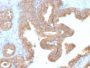

This antibody recognizes a protein of 42 kDa, which is identified as Alpha-methylacyl-CoA Racemase (AMACR), also known as p504S. It is an enzyme that is involved in bile acid biosynthesis and betbeta-oxidation of branched-chain fatty acids. AMACR is essential in lipid metabolism. It is expressed in cells of premalignant high-grade prostatic intraepithelial neoplasia (HGPIN) and prostate adenocarcinoma. The majority of the carcinoma cells show a distinct granular cytoplasmic staining reaction. AMACR is present at low or undetectable levels in glandular epithelial cells of normal prostate and benign prostatic hyperplasia. A spotty granular cytoplasmic staining is seen in a few cells of the benign glands. AMACR is expressed in normal liver (hepatocytes), kidney (tubular epithelial cells) and gall bladder (epithelial cells). Expression has also been found in lung (bronchial epithelial cells) and colon (colonic surface epithelium). AMACR expression can also be found in hepatocellular carcinoma and kidney carcinoma. Past studies have also shown that AMACR is expressed in various colon carcinomas (well, moderately and poorly differentiated) and over expressed in prostate carcinoma.Primary antibodies are available purified, or with a selection of fluorescent CF® Dyes and other labels. CF® Dyes offer exceptional brightness and photostability. Note: Conjugates of blue fluorescent dyes like CF®405S and CF®405M are not recommended for detecting low abundance targets, because blue dyes have lower fluorescence and can give higher non-specific background than other dye colors.

Positive Control

HEK cells or Prostate Adenocarcinoma

Higher concentration may be required for direct detection using primary antibody conjugates than for indirect detection with secondary antibody|Immunohistology (formalin): 1-2 ug/mL for 30 minutes at RT|Staining of formalin-fixed tissues requires boiling tissue sections in 10 mM citrate buffer, pH 6.0, for 10-20 minutes followed by cooling at RT for 20 minutes|Optimal dilution for a specific application should be determined by user